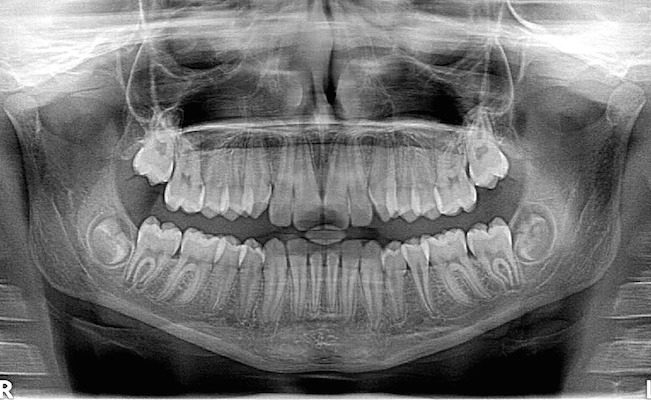

Dental x-rays help your dentist see damage and disease not obvious to the naked eye. This is the first place your doctor can tell whether your wisdom teeth will come in okay or need to be extracted, or how well your jaw has healed after a facial trauma. You need x-rays for anything below the gums. You jawbone literally holds your face together; it’s kind of important.

How often you need an oral x-ray done depends on the quality of your dental health, your disease risk, and how old you are. Children need x-rays more often because their teeth and jaws continue to grow, and their teeth are more prone to tooth decay.

If you are a new patient, we may do x-rays to get a better understanding of your dental health. This gives us a more complete picture of any care you might require in the future. We’ll look for signs of tooth decay, examine the health of your gums, and examine the quality of your tooth development.